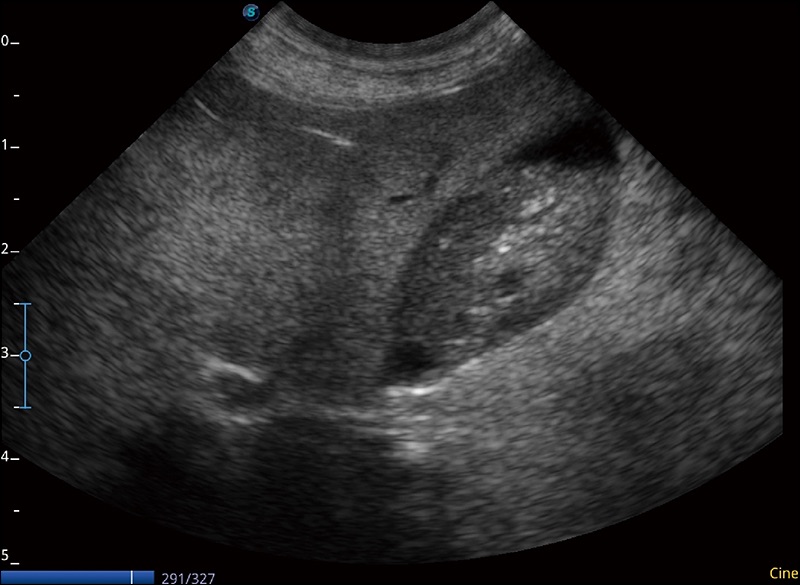

α1卓越的图像质量和便捷的工作流程,使每位宠物医生都能轻松扫查。其全面的兽用应用功能和紧凑型的结构设计,可以满足动物检查的多种需要。专业的预设检查模式和多领域测量软件包有助于为不同类型的动物提供检查, 让宠物医生能够出色的完成工作。

穿刺针增强

高清显示穿刺进针情况

连续波多普勒成像CW

为心脏功能评估提供更多诊断信息